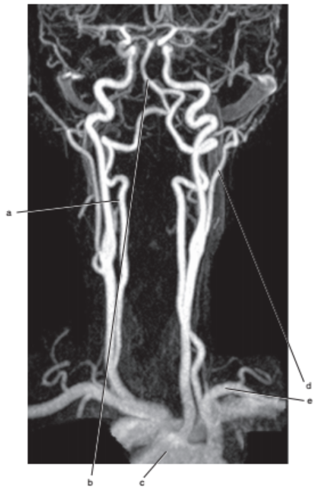

What is letter a ?

Vertebral artery

Internal jugular vein

What is letter e ?

Carotid bifurcation is -

superior border of thyroid cartilage

The common carotid artery bifurcates at the level of -

C3-C4

Carotid sinus/bifurcation